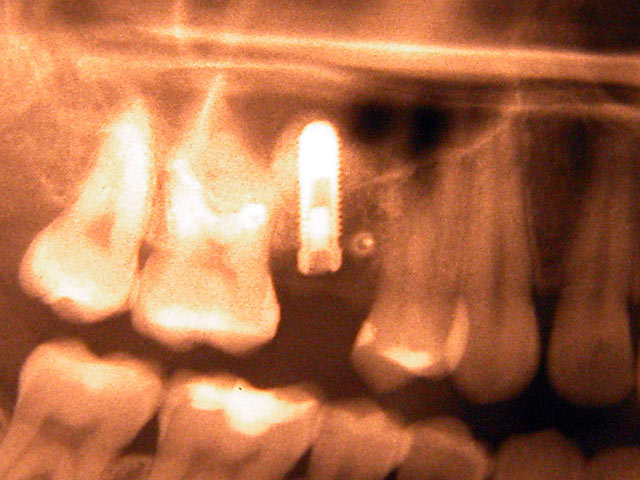

Die folgenden Patientenfälle sollen Ihnen einen Einblick in die Möglichkeiten der modernen Implantation geben.

Implantation – Patientenbeispiel 1: